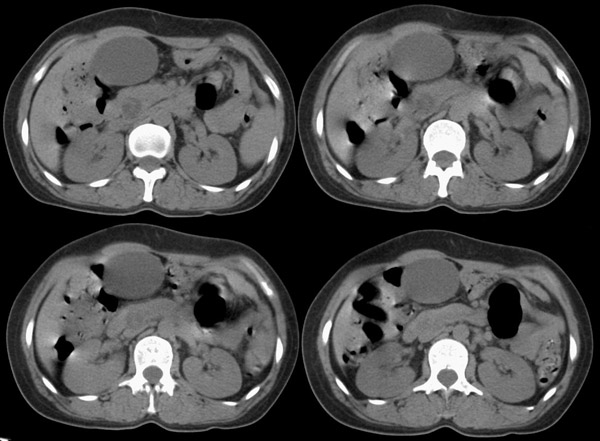

局部1mm薄层重建:

整个胆道系统内可见多发蛔虫钙化改变,胆道扩张.

支持胆道内蛔虫钙化及胆总管远端梗阻性病变多为结石并胆道扩张.

胆总管结石(蛔虫钙化)并低位胆系梗阻